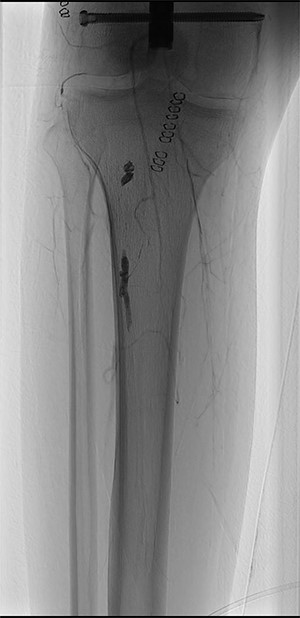

An emergency vascular surgery consultation was required. Upon our arrival, the foot was hypothermic and pale, with pain and paraesthesia. At the angiography, near occlusion of the SFA at its middle third was found, with concomitant occlusion of the popliteal artery and of the leg arteries (Fig. 2).

ONYX 34 residuals in the distal popliteal artery and in the tibioperoneal trunk obstructing blood-flow in the right lower limb.

The CW-Doppler examination showed absence of distal arterial flow and an urgent surgical revascularization was unavoidable.